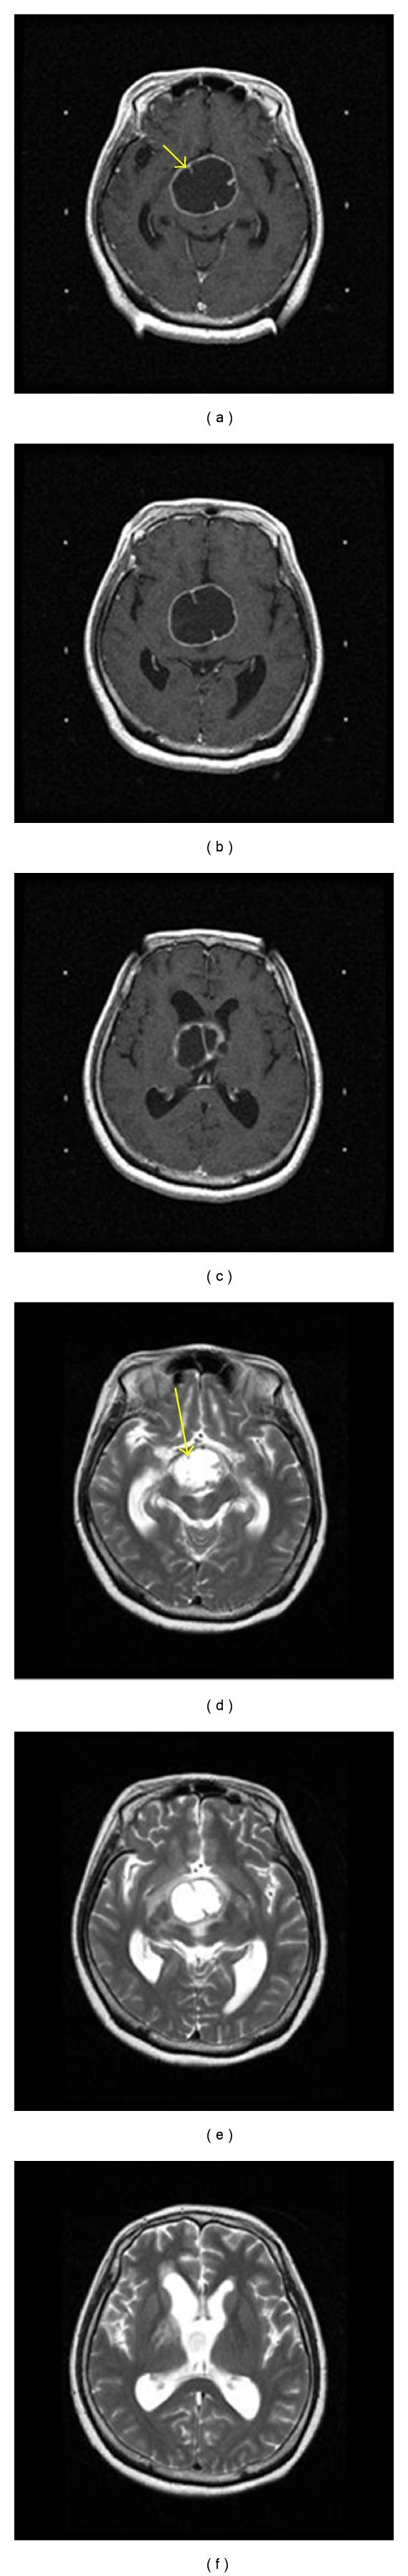

https://cdn.ncbi.nlm.nih.gov/pmc/blobs/3e02/3177458/82819626a398/IJTA2011-353405.001.jpg